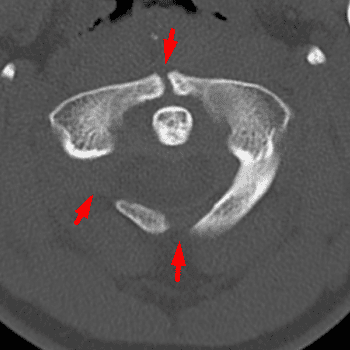

Congenital Anomalies of C1

Case 13

Free